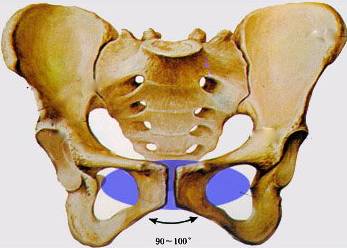

骨盆倾斜怎么判断哪些人容易骨盆倾斜附2招自我矫正法

健康坏习惯让骨盆经历了啥

骨盆倾斜原因分析,你正在用哪个方式伤害自己的骨盆?——徐州脊柱侧弯

其它 盆骨变形的危害 写美篇一,骨盆变形容易导致脊椎弯曲,压迫神经